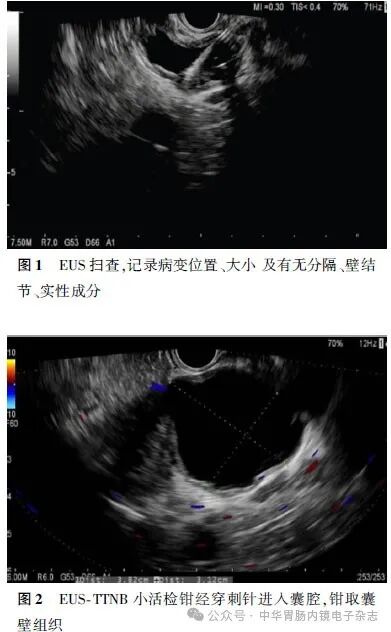

2.EUS相关操作:主要由3名经验丰富的内镜医师进行。操作流程可大致分为2步:(1)线阵EUS检查:在静脉麻醉下对患者行EUS检查,观察并记录囊肿的位置、大小、囊壁厚度、有无分隔、有无壁结节、胰管扩张情况以及囊内有无实性成分(图1);(2) EUS-TTNB:采用19G细针经胃或十二指肠穿刺进入囊腔。将活检钳经穿刺针送入囊内。用活检钳夹取囊壁组织,随后退出活检钳,收集样本(图2),重复该步骤3~4次。